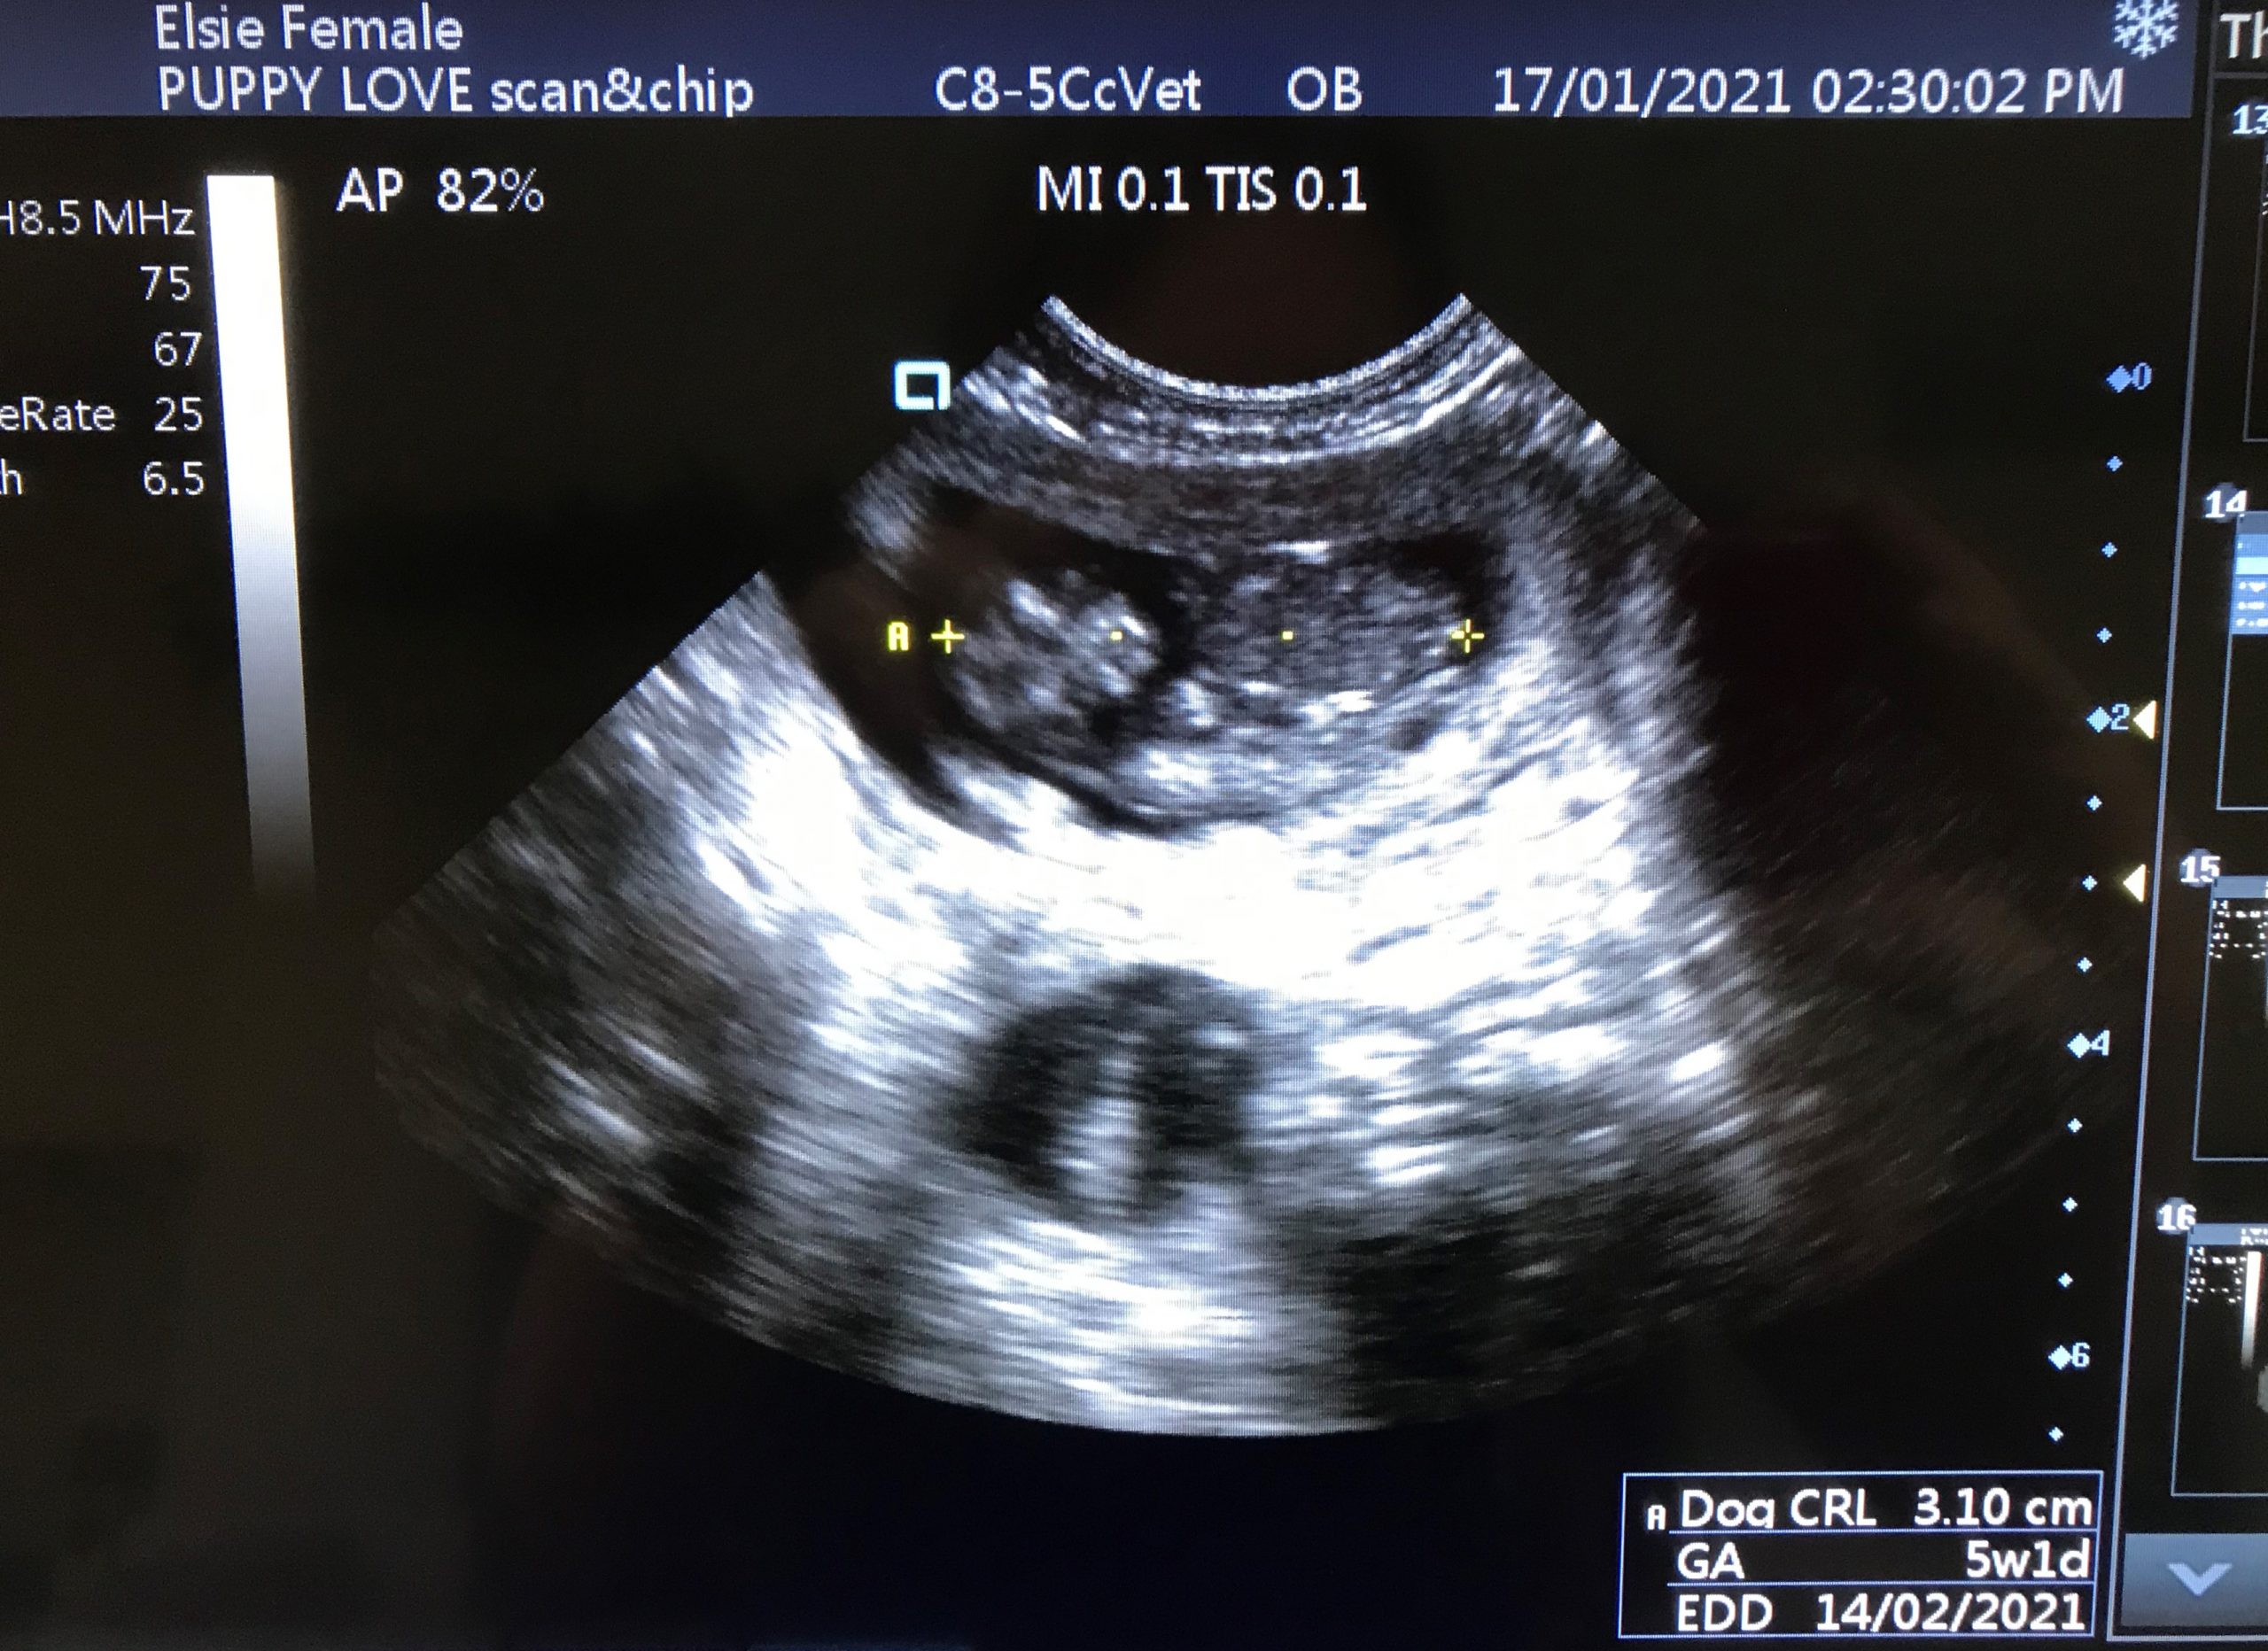

Multiple gestational sacs seen with heartbeats. Approximately 4/5.

CRL measured, gestational age 36days. EDD 14.02.21

Scan confirms first scan GSD measurements for gestational age.

Puppies developing as expected. Foetal heartbeats clearly visible. Image 1. Biparietal diameter (BPD) suggests foetal GA 39 days compared with measurements from first two scans which put Elsie around 42